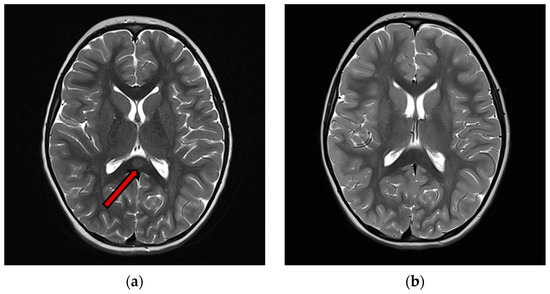

3.5. Instrumental Examination

Hyponatremia was found in 12 patients (63%), normal sodium levels in 7 patients (37%). C-reactive protein (CRP) was high in 13 patients (68%). White blood cells were high in 5 patients (26%). Only 9 patients underwent lumbar puncture, and CSF cell count was normal for all of them (100%). An EEG recording was performed in 14 patients. Nine patients (64%) showed an abnormal EEG. Almost half of these patients (4/9 cases) exhibited a slow background activity (BA). In two patients, EEG showed epileptic anomalies and in four EEG recordings there were slow anomalies, without clear epileptic abnormalities. A contrast-enhanced brain MRI with T1, T2-weighted sequences, DWI and FLAIR studies at the onset was performed in all patients. Eighteen patients (95%) showed type I lesions (Figure 2), while 1 patient (5%) had type II lesions. A follow-up MRI was available in 13 patients within a time interval ranging from 1 week to 10 months from the acute episode. In all these cases, the follow-up contrst-enhanced MRI showed complete resolution of the previously observed lesions, including on the T1, T2-weighted sequences DWI and FLAIR studies.

Figure 2. (a) T2 images of acute phase of MERS Type 1 (b) T2 weighted images of the same patient of acute phase of MERS type 1. An ovoid high signal area is observed in the midmedulla of the body of the corpus callosum (arrow), 3 months after the previous, showing complete resolution of the lesion.